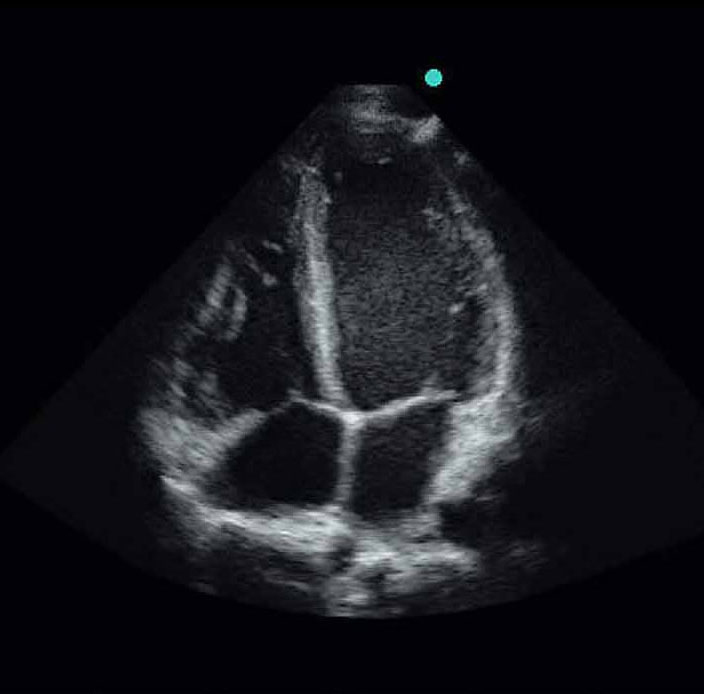

Cardiology 1 Image